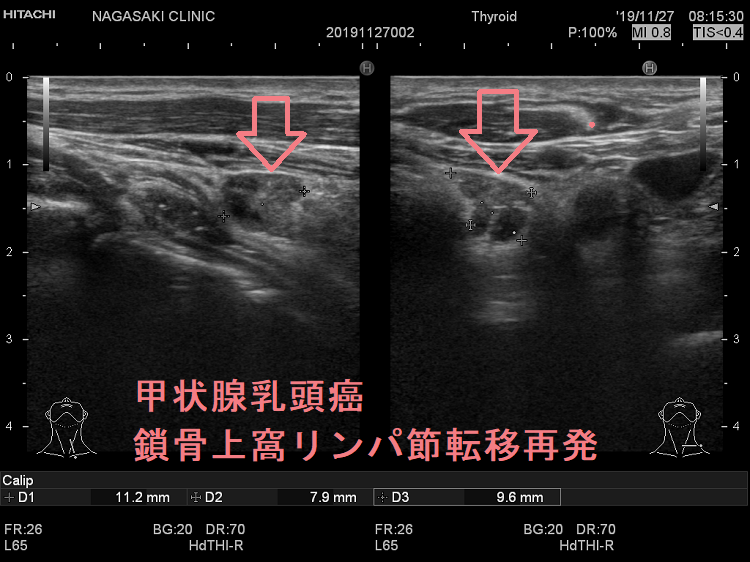

甲状腺乳頭癌の鎖骨上窩リンパ節転移再発

甲状腺乳頭癌鎖骨上窩リンパ節転移再発

甲状腺乳頭癌の鎖骨上窩リンパ節転移再発 超音波(エコー)画像

鎖骨上窩は予防的リンパ節郭清(前頚部リンパ節郭清)の範囲外につき、術後リンパ節再発のピットフォールとなります(意外とよく見つかります)。

甲状腺乳頭癌が左鎖骨上窩リンパ節に転移して再発すると、左静脈角から血流に乗って全身へ運ばれ、遠隔転移を来します。左鎖骨上窩の転移リンパ節をウィルヒョウリンパ節、左鎖骨上窩リンパ節転移をウィルヒョウ転移と言います。